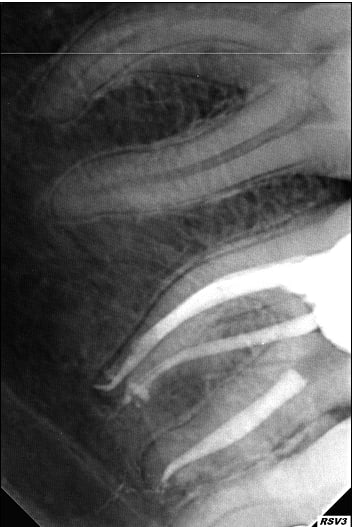

Moins impressionnant que les cas d'esthétique des pages précédentes mais je suis content de mon endo 4 canaux ;)

O 02e7d4f0bd462f70 0 cmqift - Eugenol

O 1958718cc4fe96b5 0 bjixou - Eugenol

As-tu une radio de cette dent reconstruite ?

J'espère que tu as prévu une élongation coronaire en distal.

ça va, il y a de l'os.

Edit: c'est peut-être aussi un artéfact avec le métal du clamp, bien que sur la 1ere radio on semble bien être en sous-crestal.